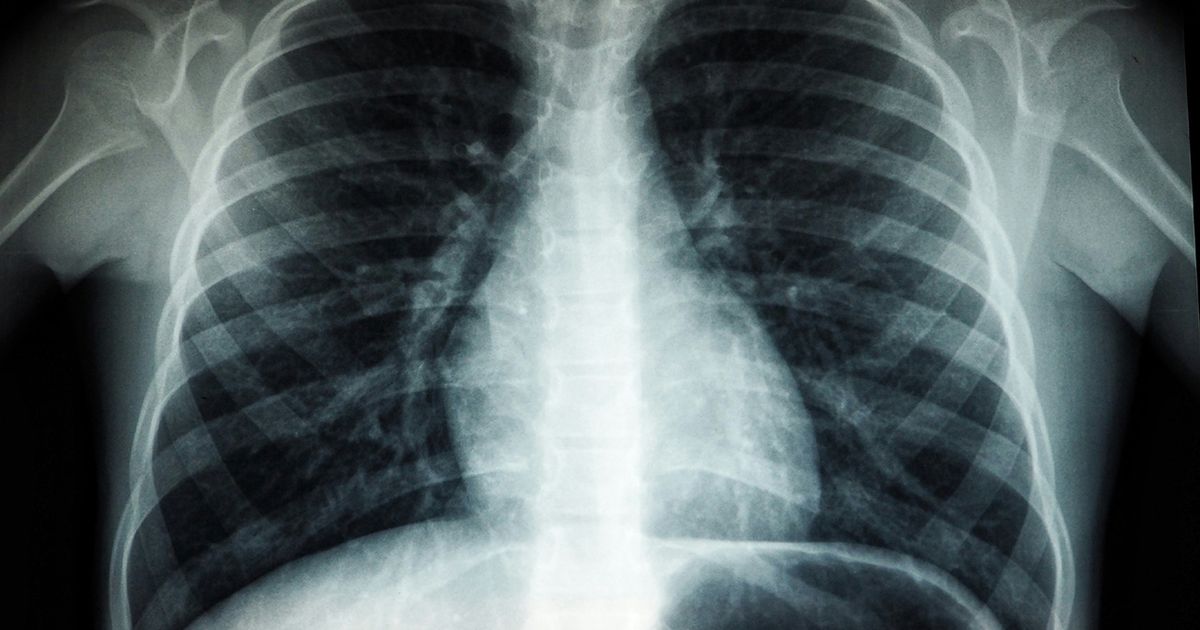

A recent study from researchers at Duke University has significantly changed our understanding of one of the most lethal types of lung cancer.

This Wednesday, the team published findings indicating that small cell lung cancer (SCLC) likely originates in basal stem-like cells instead of specialized lung cells known as neuroendocrine cells.

According to the American Cancer Society, SCLC accounts for about 10 to 15% of all lung cancers, with around 30,000 new cases diagnosed annually.

Regarded for its rapid growth, the cancer often spreads to other body parts before detection. The ACS notes that the 5-year survival rate for SCLC is below 10%, owing to its aggressive nature.